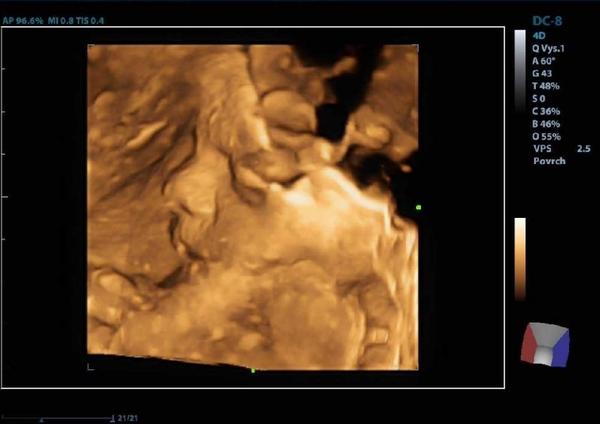

@tercasv ony ty cizí fotky na internetu jsou něco jiného, než když pak člověk vidí toho svého cvrčka 🙂 Mě tedy zase tak moc neoslovily přímo ty fotky - byť se nám povedly docela hezky, ale líbil se mi ten zážitek. Je vidět, jak se tam miminko tváří, jak zívá, dělá ksichtíky........🙂

Musím říct, že to bylo super. Přesto, že nejsem zrovna hubená a mám placentu na přední straně, tak bylo mimčo krásně vidět. Oproti těm skoro mazaninám od gynekologa nesrovnatelné....

Takže doporučuju. Myslím si, že to tatínkovi pomůže vytvořit si i nějaký vztah k mimču. Když ho takhle uvidí na videu, jak se tam hýbe, zívá, strká si pěstičku do pusinky atd. 🙂